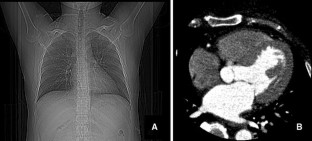

Fig. 2